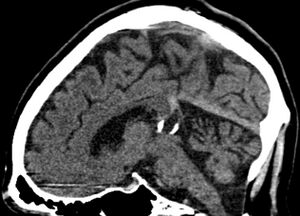

Calcified cyst of pineal gland in CT. Sagittal MPR. |

كيسة الغدة الصنوبرية pineal gland cyst هو تكيّس حميد (غير خبيث) في الغدة الصنوبرية، a small endocrine gland in the brain. Historically, these fluid-filled bodies appeared on 1-4% of magnetic resonance imaging (MRI) brain scans, but were more frequently diagnosed at death, seen in 4-11% of autopsies.[1] A 2007 study by Pu et al. found a frequency of 23% in brain scans (with a mean diameter of 4.3 mm).[1]